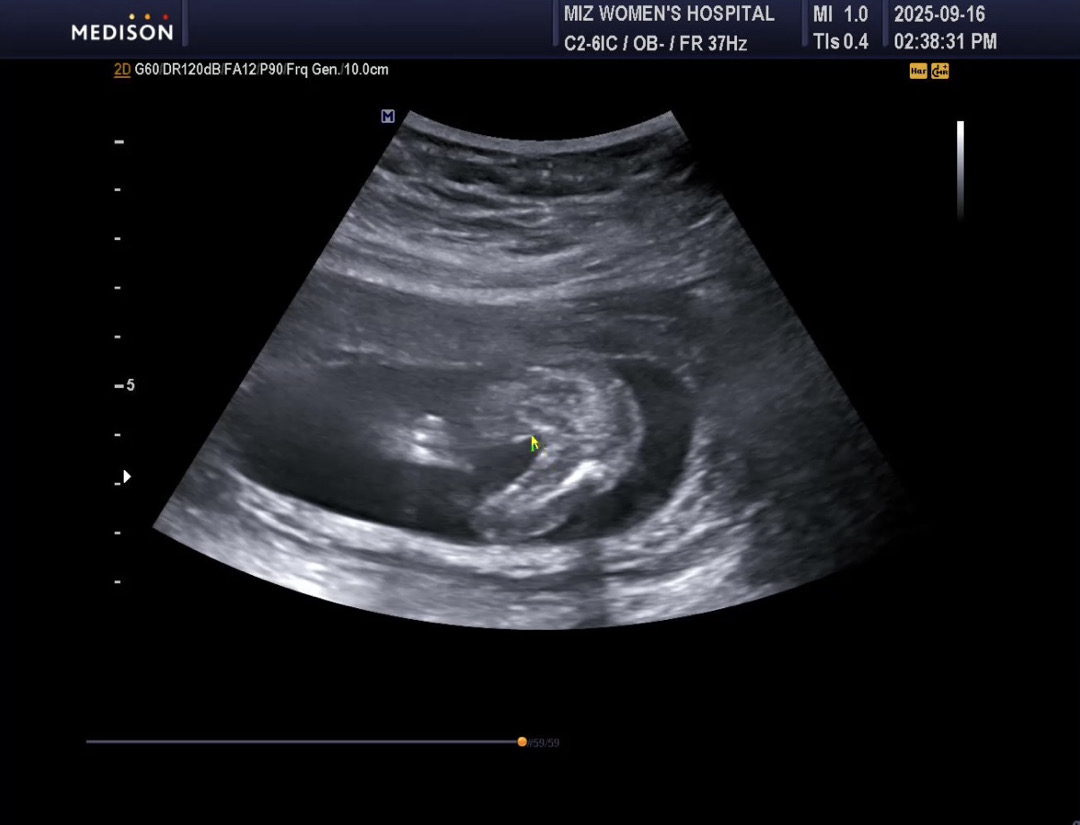

16주차 성별

부모님께 젠더리빌 하려고 하는데 이정도면 반전없이 딸이겠죠?

딸이네요 반전없어요